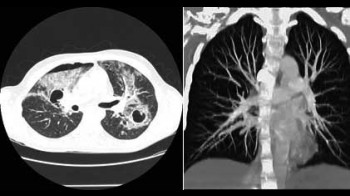

CT screening (rano otkrivanje) karcinoma pluća

Karcinom pluća je najčešći karcinom kod muškaraca, pa se ranom otkrivanju te bolesti pridaje velika važnost. Uvođenje višeslojnog CT-a (MSCT) u kliničku praksu omogućilo je i screening (rano otkrivanje) karcinoma pluća. Pregled je namijenjen onima koji su visokog rizika za karcinom pluća i omogućava otkrivanje izrazito malih čvorova u plućima, koji mogu biti prisutni, a da nisu vidljivi na standardnom rtg snimku pluća. Rano otkrivanje ovih promjena može dramatično poboljšati uspješnost liječenja karcinoma pluća.

Kome je potrebno ovo snimanje?

CT screening pluća se preporučuje uraditi pušačima starijim od 60g, a čiji pakovanje-godine index je veći od 10 (pakovanje-godine index se dobije tako što se pomnoži broj godina pušenja sa brojem kutija cigareta koje se ispuše svaki dan: preko 80% karcinoma pluća se dijagnostikuje u ljudi starijih od 60g). Drugi kandidati za pregled su pacijenti starosti 50-60g, koji imaju pakovanje-godine index 20-30 ili s drugim riziko-faktorima kao što je izlaganje azbestu ili hronična opstruktivna bolest pluća.